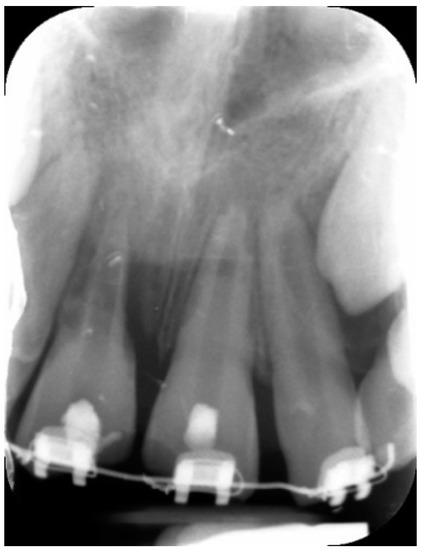

External Root Resorption Management of an Avulsed and Reimplanted Central Incisor: A Case Report

2. Case Report